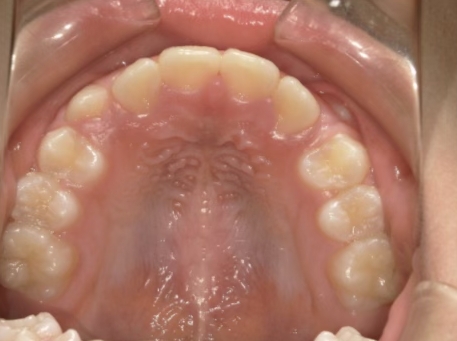

治療中③ 小4:9y10m

咬合治療用モノブロック装置(筋機能的咬合誘導装置)スタート

*就寝時に使用するモノブロック装置(筋機能的咬合誘導装置)